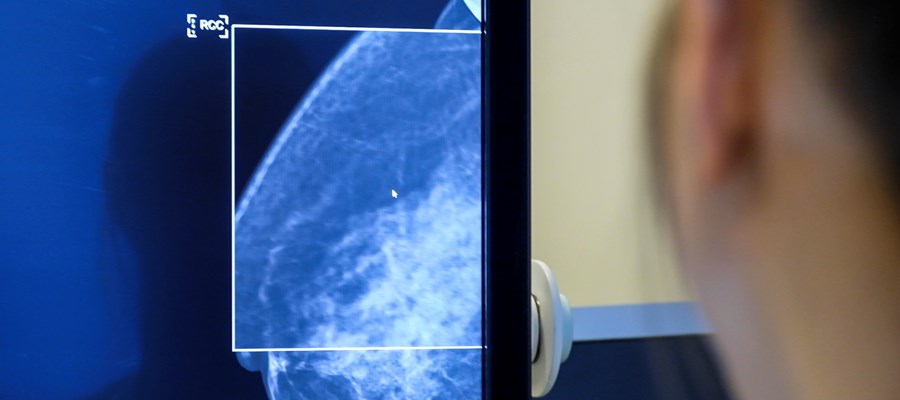

Mer än var femte kvinna i Sverige uteblir från sin mammografi. En ny undersökning som Cancerfonden låtit göra visar att de flesta som inte dyker upp antingen har glömt bort sin tid, inte har en mottagning tillräckligt nära eller inte har kunnat ta ledigt från jobbet. En klar majoritet minns heller inte att de fått en påminnelse.

Varje år får omkring 8 500 kvinnor i Sverige beskedet att de har bröstcancer. Tack vare det nationella mammografiprogrammet som började införas för närmare 40 år sedan upptäcks idag betydligt fler fall i ett tidigt skede, vilket gör att allt fler kvinnor överlever sin bröstcancerdiagnos. Cancerfondens granskning visar dock att det fortfarande råder stora geografiska och socioekonomiska skillnader i mammografideltagandet över landet. I vissa kommuner uteblir mer än var tredje kvinna från sin undersökning medan andra kommuner har ett deltagande på över 90 procent. I snitt uteblir mer än var femte kvinna (22 procent) från sin mammografi.